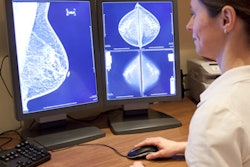

Regular breast cancer screening with mammography for younger women translates into a lower stage at breast cancer diagnosis and less-extensive treatment, according to a study published online July 9 in the Annals of Surgical Oncology.

The findings once again support a breast cancer screening approach that includes younger women, even though there is still disagreement over the value of screening in this population, wrote a team led by Dr. Soojin Ahn of Icahn School of Medicine at Mount Sinai in New York City.